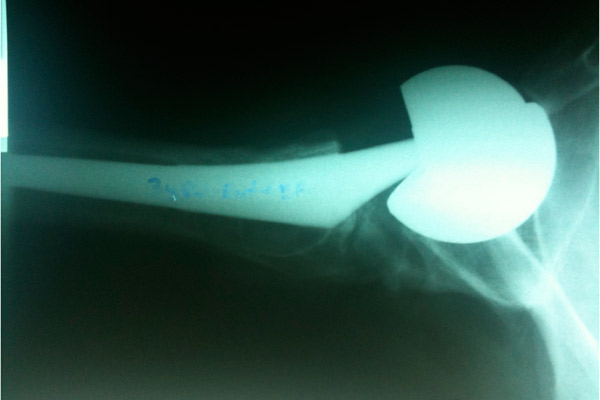

Metal-on-metal hip implants, often marketed to younger, more active patients in need of hip replacement, have been shown to have troubling side effects. Dr. Jane Shelby, director of Alaska WWAMI School of Medical Education, was a guest of Dr. Thad Woodard's "Line One: Your Health Connection" to talk about the phenomenon with Dr. Steve Tower and Dr. Michael Mayor. Listen to the podcast available through Alaska Public Media for an in-depth discussion of the procedure and what patients should know.